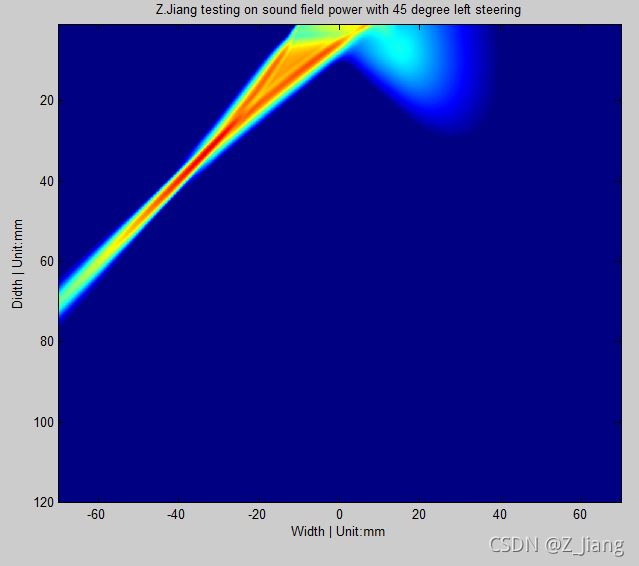

在上面的例子中,声场传播需要一段时间,为了简单便捷的表示声场,我们一般通过在空间上计算beam profile来描述波束。现在我们来仿真一个,同样的相控阵探头,3MHz的发射,但是不再是正向下,而是向左偏转45度。

我们向左偏转45度的beam profile仿真

为了便于直观查看,我调整到了一个合适的动态范围。细心的朋友能留意到,波束右侧有一个小的能量分布,那部分杂波能量我们叫为Grating Lobe(栅瓣),它会带来grating lobe artifact。如我们仿真的情况,你扫查的是左侧45度,而如果grating lobe处有组织的强反射,这部分信号将混入到我们后面的接收波束合成中,导致右侧栅瓣的组织出现在左侧45度的地方。grating lobe与发射频率,探头阵元的间距相关。一般情况下,只要它偏得比较远,在成像区域外,我们就可以不去理会它,否则你要考虑一下,这个特定的探头换个发射频率或者缩小成像区域。